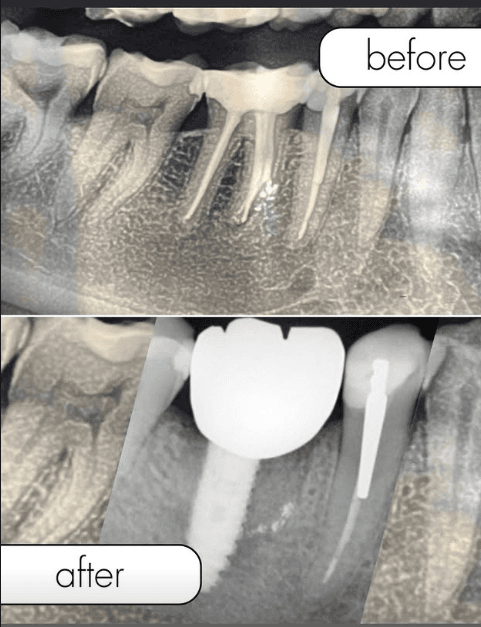

Before / After Results

Discover our patients transformations